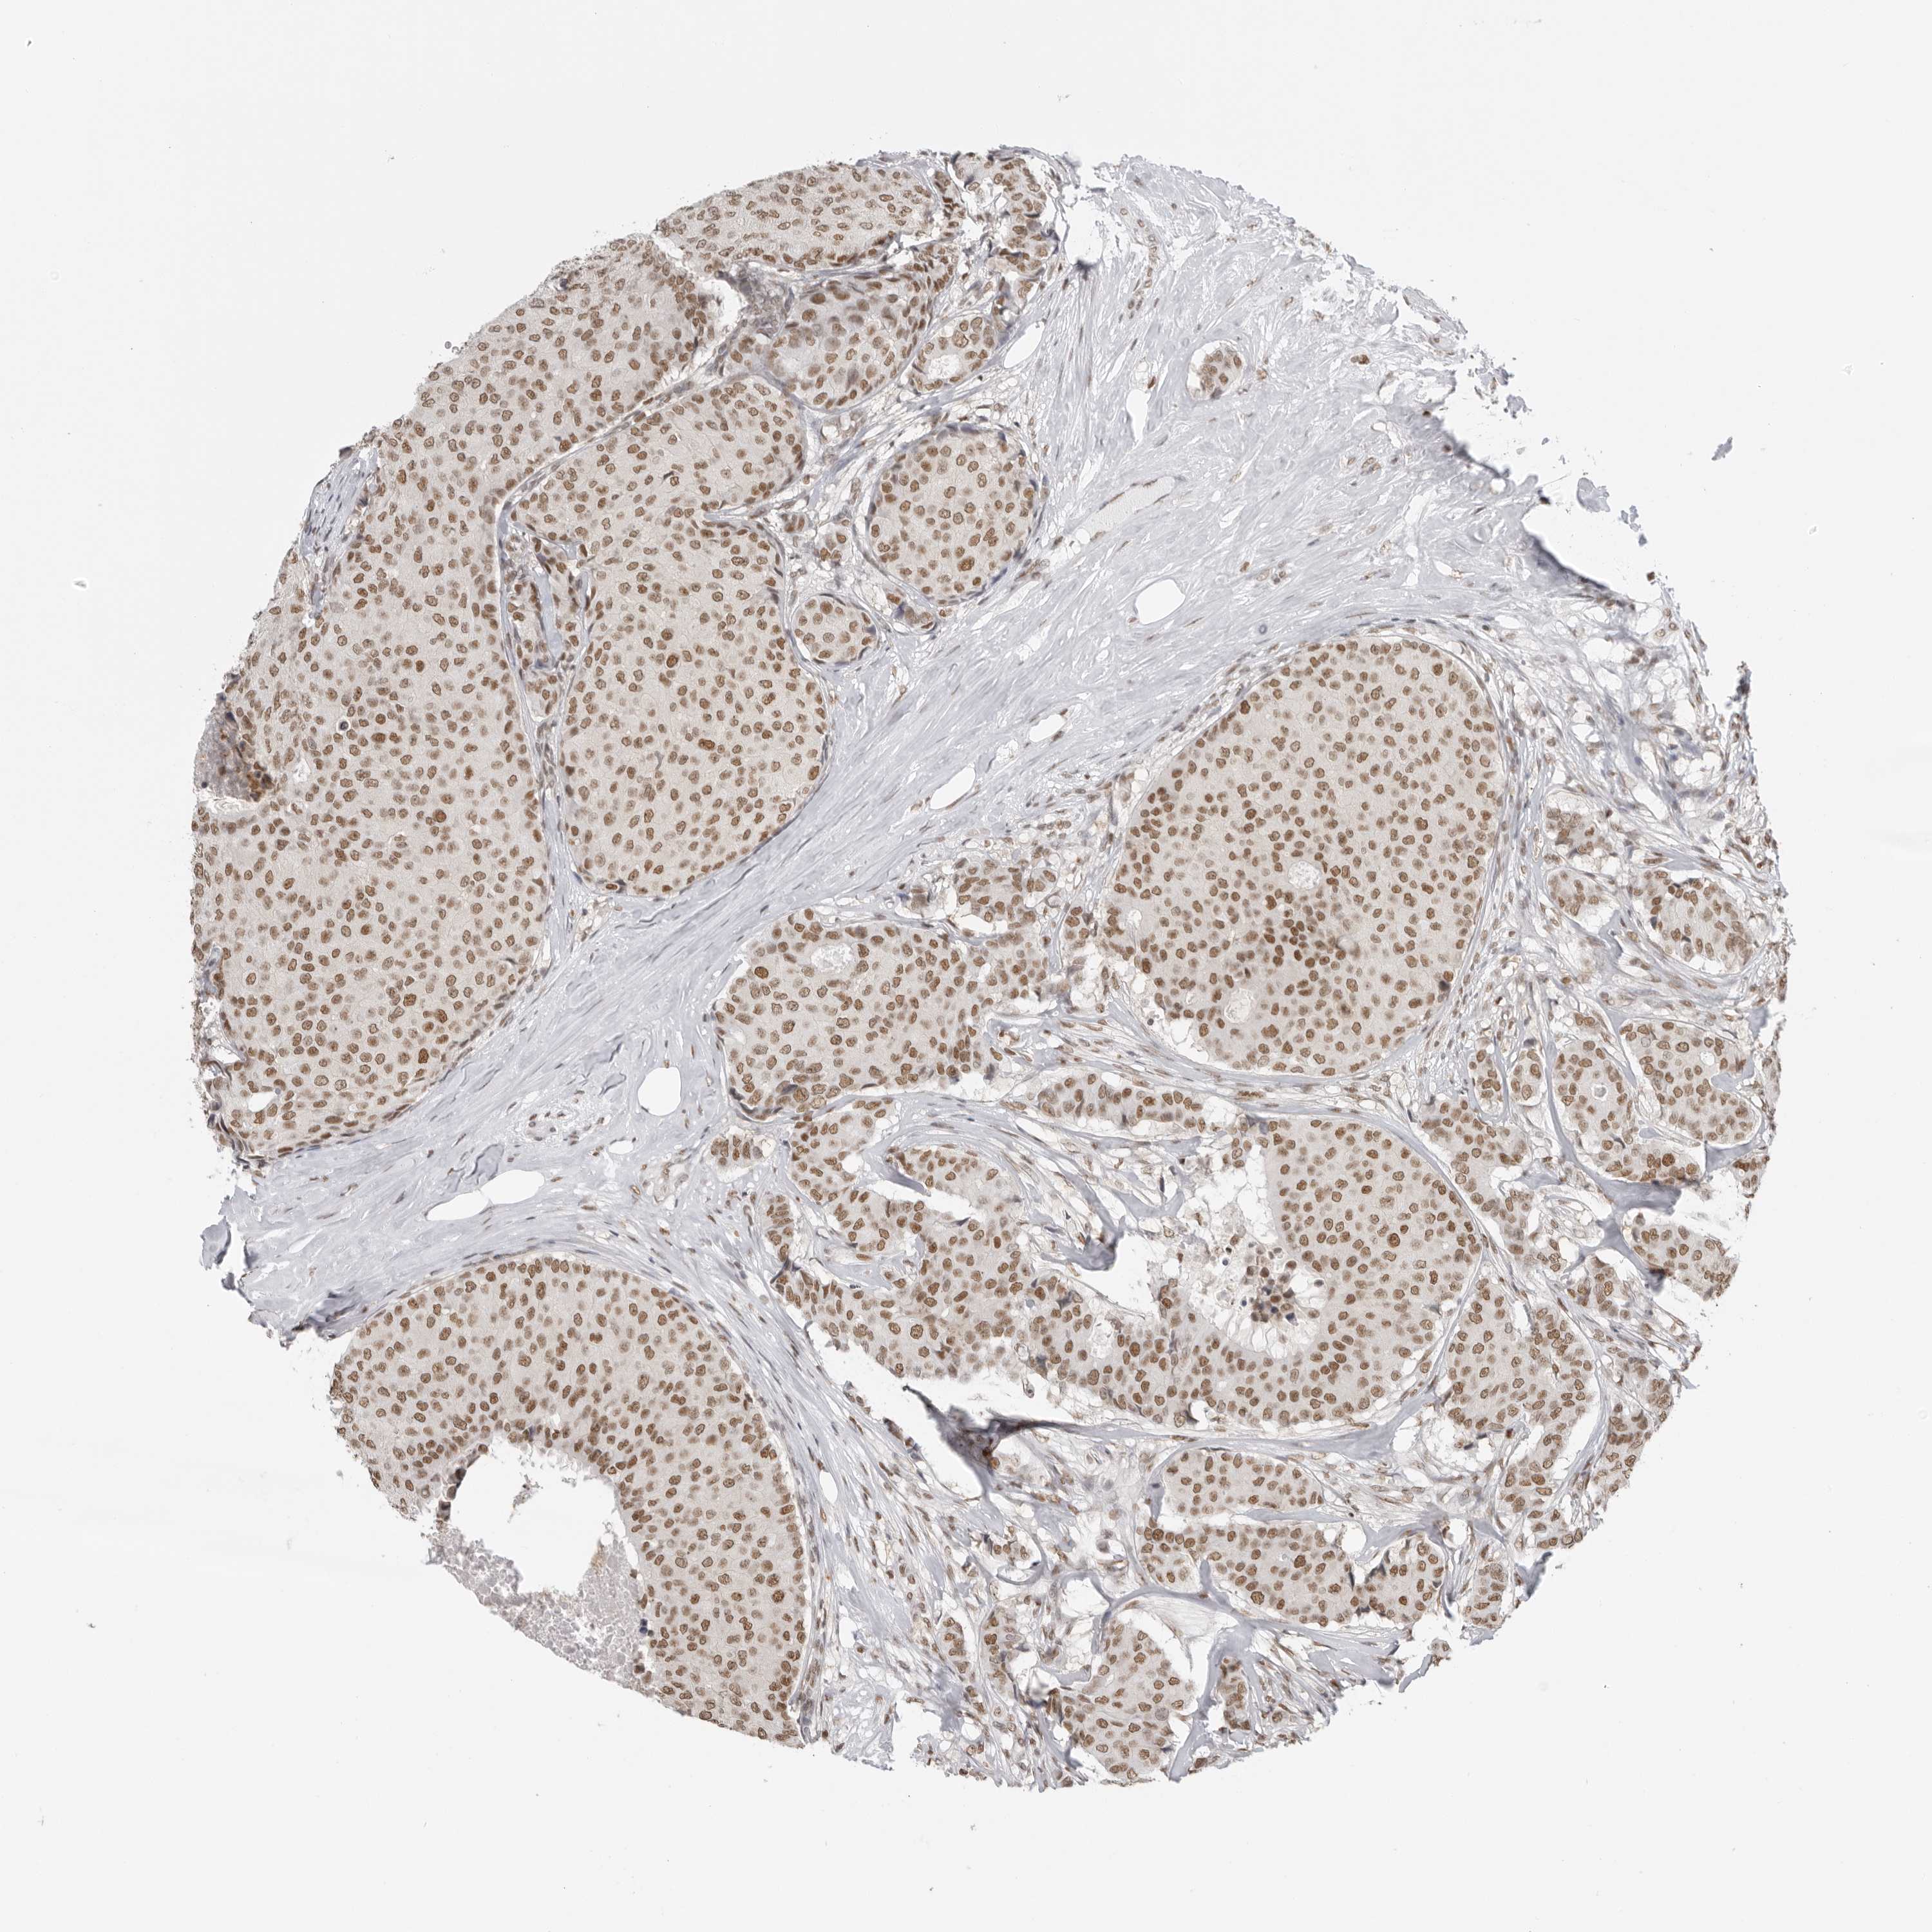

BRCA TCGA BRCA VALIDATION PROTEIN EXPRESSION